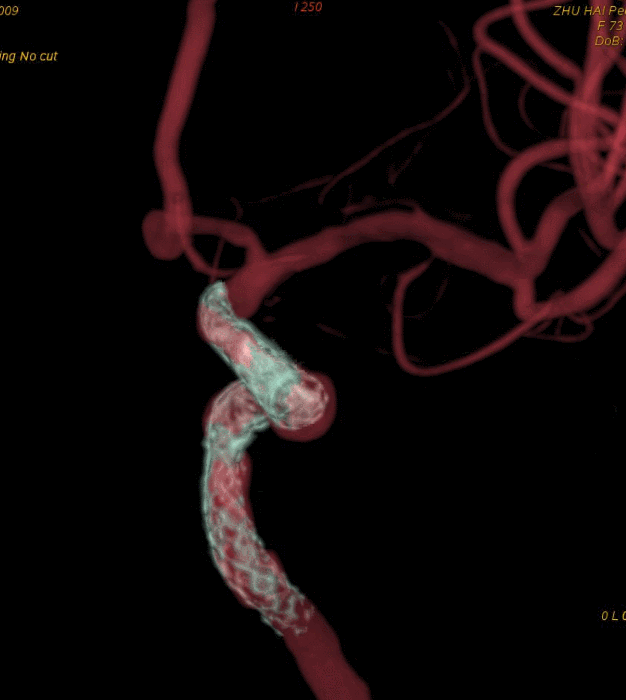

脑血管造影提示右侧颈内动脉颅内段多发动脉瘤(反主动脉弓)

脑血管造影提示右侧颈内动脉颅内段多发动脉瘤

4mm×30mm Streamline

术后4月余随访:多发动脉瘤均未见显影,远端残余轻度狭窄

术前术后对比